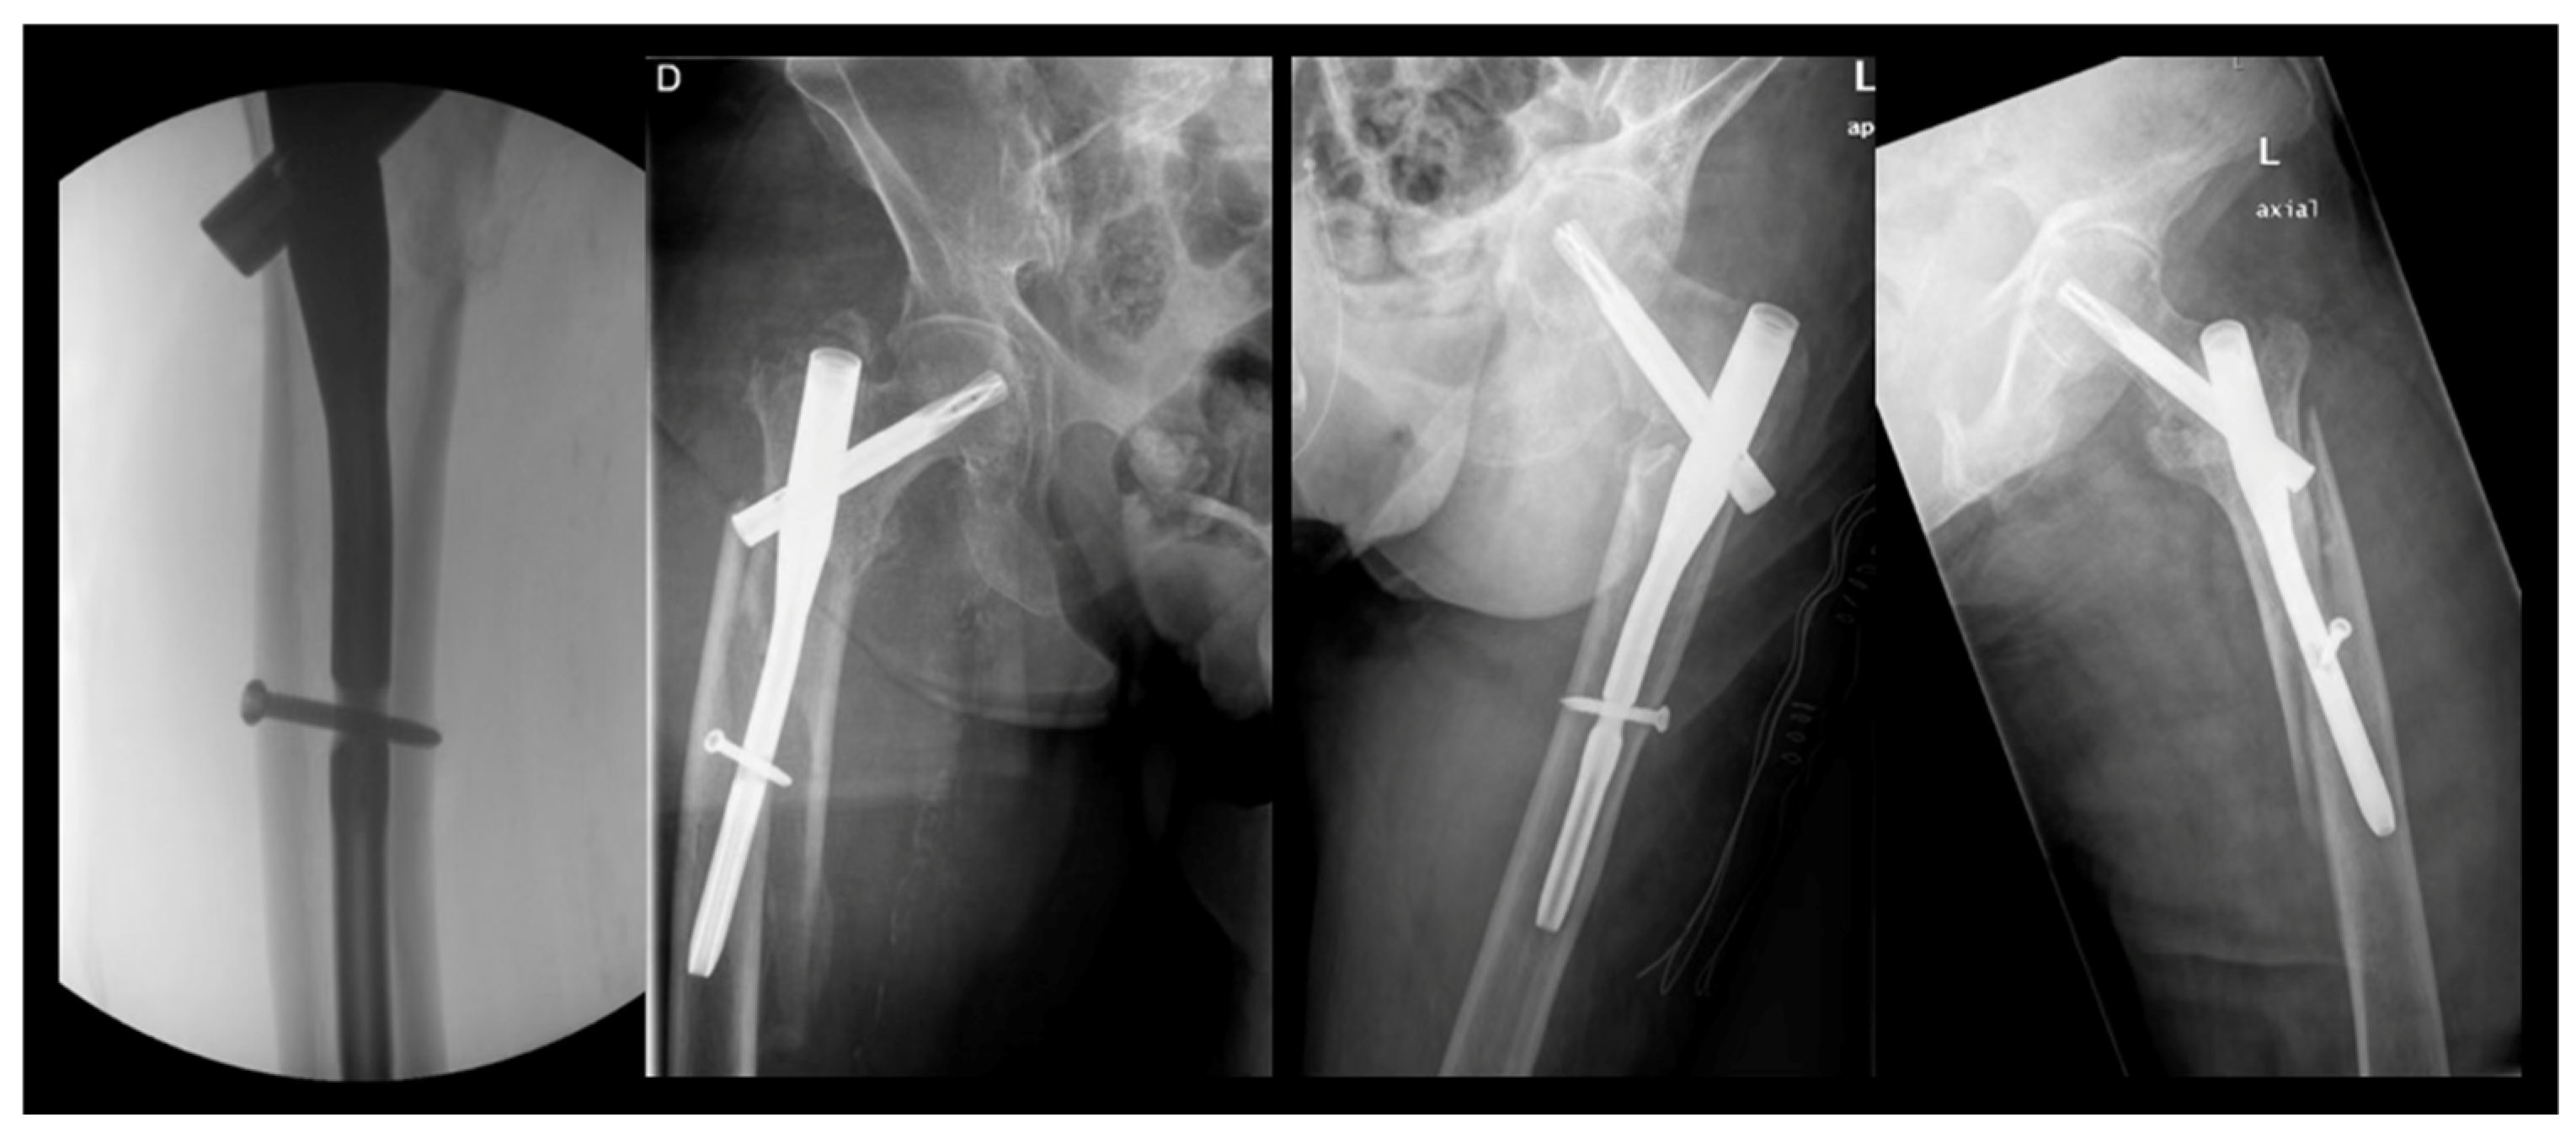

The length of the intramedullary nail is another critical consideration. Numerous studies suggest that the risk of peri-implant fractures is comparable between short and long nails [23,24,25,26]. Cinque et al. [27] found no significant differences in the rate of peri-implant fractures between the two lengths, favoring short nails for pertrochanteric fracture treatment due to benefits such as a reduced blood loss, shorter surgery duration, and lower complication rates. Our study exclusively analyzed short cephalomedullary nails in initial fractures. Regarding distal locking, all patients in our cohort had distally locked intramedullary nails, with dynamic locking employed in the majority (88%). Skála-Rosenbaum et al. [28] concluded that distal locking helps prevent peri-implant fractures and recommended its use, while considering the possibility of non-locked intramedullary nails in certain stable pertrochanteric fractures, provided the nail adequately fills the intramedullary cavity. Notably, 15% of the peri-implant fractures in our study occurred right at the level of the distal locking screw, indicating a need for further evaluation. We believe there may be a relationship between these fractures and the force applied by the surgeon when tightening the distal locking screw, particularly given that, in most cases, the distal screw barely extended through the second femoral cortex. This positioning may act as a stress riser, creating a focal point of weakness in the femur.

With 26.4% of patients experiencing fractures within 2 months post surgery of the index fracture, we advise a careful surgical technique to further improve outcomes and minimize the risk of PIFFs. The following strategies can be adopted. Surgeons should avoid overtightening distal locking screws against the outer cortical bone of the femur. Utilizing short femoral nails that do not impinge upon the anterior cortical bone (or considering the use of anatomical left and right nails) can also be beneficial. Employing overlapping techniques when other implants are present in the femur is advisable, while preventing the errors and outcomes presented in Figure 4, Figure 5 and Figure 6. Furthermore, using protective medications for bone fragility, such as anti-resorptives, following the diagnosis of an initial fracture (index fracture) may enhance patient outcomes.

Figure 6. Error #3—the overtightened screw. The correct measurement of the distal locking screw is crucial. When the screw length is underestimated, the surgeon might overtighten it in an attempt to reach the second cortical of the femoral diaphysis. In such cases, the combination of the weakness created by the screw hole and the stress riser caused by the overtightened screw can lead to a fracture.